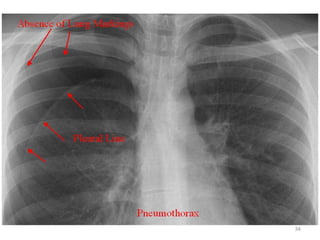

• Chest X-ray PA view showing the sharply

defined edge of the deflated lung with

complete translucency (no lung markings, no

vascular markings) between this and the chest

wall in the Rt side with shifting of

mediastinum to left.

• Suggestive of Rt Tension Pneumothorax

Pneumothorax